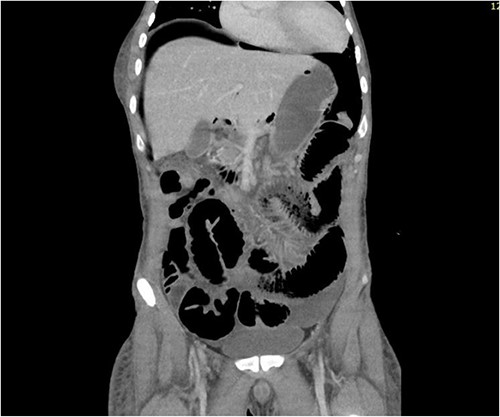

CT abdomen revealed a large amount of free air throughout the abdomen, mostly localized anterior, but also perihepatic, perigastric, paracolic, and perisplenic (Figs 1 and 2).

CT abdomen showing a large amount of free air mostly localized anterior.